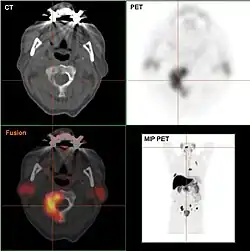

- F-18-Cholin-PET/CT

Osteolytische Knochenmetastase im zweiten Halswirbelknochen (Axis) eines metastasierten Prostatakarzinoms -

Osteoplastische Knochenmetastase eines metastasierten Prostata-Karzinoms im Hüftgelenk -

CT einer Prostatakrebs-Metastase im linken Schambein (im Bild rechts) -

Cholin-PET derselben Metastase im Schambein -

Fusionsbild aus CT und Cholin-PET der Prostatakrebs-Metastase im linken Schambein